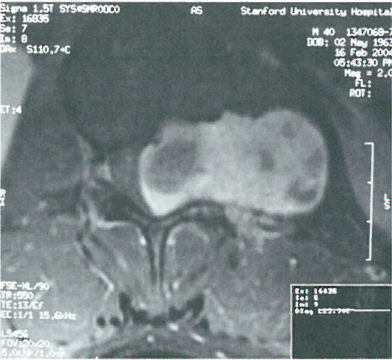

美国看病机构爱诺美康了解到,MRI检查可以看到在L1水平有一累及椎管内外的明显强化的肿块(图)。手术采用的是单纯后路切除,术中切除椎板及小关节后暴露肿瘤(图3)。

图1 L1水平典型的哑铃型肿瘤,瘤内有囊性成分。